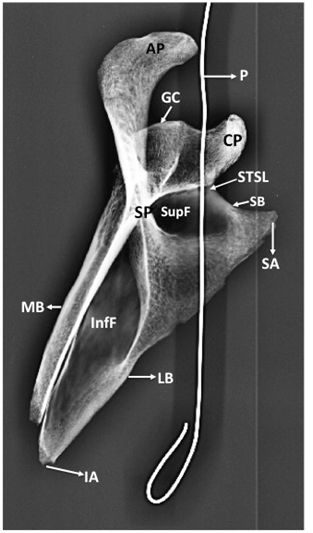

Figure 2 Posterior view of bony scapula showing.

SSF, suprascapular foramen; STSL, superior transverse scapular ligament; P, probe in SSF; CP, coracoid process; AP, acromian process; SP, spinous process; GC, glenoid cavity; SupF, supraspinous fossa; InfF, infraspinous fossa; LB, lateral border of scapula; SB, superior border of scapula; SA, superior angle of scapula

The circumference of the bony foramen was 17mm. Its superior margin was made of ossified STSL. The body of scapula constituted the inferior and medial margin. Root of coracoid process formed the lateral margin of the foramen. The maximum vertical diameter of the foramen was 7mm and the maximum transverse diameter was 4mm. The SSF was oval in shape. It was not present at the usual site but instead presented at the root of coracoid process. The margins of SSF were smooth and the foramen formed a communication between supraspinous and subscapular fossa. This was confirmed by passing a probe through the foramen. The ossified STSL, forming the superior margin of the SSF was oblique and fan shaped. It converted the suprascapular notch into a foramen. The width of STSL at the root of coracoid process was 3mm and its width at the lateral most end of superior border of scapula was 5mm. The patency of SSF was established by taking a radiological picture after putting a probe through the foramen (Figure 5) (Figure 6).

Figure 5 X-Ray of Scapula (AP view) showing. STSL, superior transverse scapular ligament; P, probe in suprascapular foramen; CP, coracoid process; AP, acromian process; SP, spinous process; GC, glenoid cavity; SupF, supraspinous fossa; InfF, infraspinous fossa; LB, lateral border of scapula; SB, superior border of scapula; MB, medial border of scapula; SA, superior angle of scapula.

STSL, superior transverse scapular ligament; P, probe in suprascapular foramen; CP, coracoid process; AP, acromian process; SP, spinous process; GC, glenoid cavity; SupF, supraspinous fossa; InfF, infraspinous fossa; LB, lateral border of scapula; SB, superior border of scapula; MB, medial border of scapula; SA, superior angle of scapula